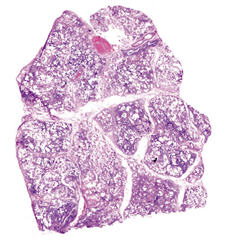

- Морфологический диагноз ОИП рекомендуется выставлять больным с ИЗЛ при выявлении в биоптатах легочной ткани гетерогенных изменений архитектоники легких за счет участков плотного фиброза, часто с формированием «сотовых» структур, в сочетании с участками менее пораженной (или сохранной) паренхимы и при отсутствии признаков альтернативного заболевания легких [1].

Комментарии: Эти патогистологические изменения обычно наиболее выражены в субплевральных и парасептальных зонах (Рис. 4). Интерстициальное воспаление обычно выражено умеренно, в виде очаговых инфильтратов, состоящих из лимфоцитов и плазматических клеток. В зонах фиброза могут встречаться так называемые фибробластические фокусы, состоящие из пролиферирующих фибробластов и миофибробластов (Рис. 5). «Сотовые» структуры представляют собой кистозные полости с фиброзной стенкой, обычно выстланные бронхиолярным эпителием, которые могут содержать слизь и клетки воспаления (Рис. 6).

Рис. 4. Обычная интерстициальная пневмония: участки фиброза в подплевральных и парасептальных зонах

Рис. 5. Обычная интерстициальная пневмония: миофибробластический фокус в месте перехода респираторной бронхиолы в альвеолы

Рис. 6. Обычная интерстициальная пневмония: "сотовые" структуры